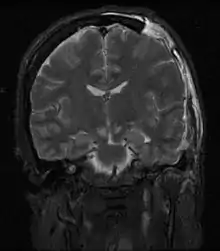

Дислокація мозку — патологічний стан, клінічний синдром, який виникає внаслідок зміщення одних структур мозку відносно інших.

При підвищенні тиску в певному відділі мозку і черепної коробки (поява області дістензії) відбуваються процеси зсуву частин головного мозку в межах субарахноїдального простору. Таким чином при різних по етіології гострих патологічних процесах у дислокаційних синдромах беруть участь одні й ті ж анатомічні структури зі стереотипним клінічним проявом. Іншими словами, клінічна картина гострого дислокаційного синдрому не залежить від етіології процесу. Різниця ж у клінічному прояві в різних хворих залежить від темпу його розвитку, локалізації та об'єму.

Справа в тому, що дислокаційні синдроми по суті є внутрішніми грижами мозку, тобто впинання його відділів в отвори і щілини, утворені кістками і твердою мозковою оболоною. Розрізняють 3 ступеня дислокації мозку: випинання, вклинення і утиск. Існують бічні та аксіальні (по осі стовбура) дислокації мозку.